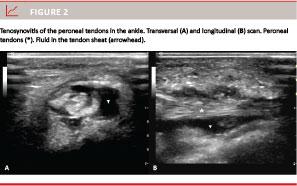

Tenosynovitis is defined as hypoechoic or anechoic, thickened tissue with or without fluid in the tendon sheath, which is seen in two perpendicular planes and which may exhibit Doppler signal [7] (Figure 2).